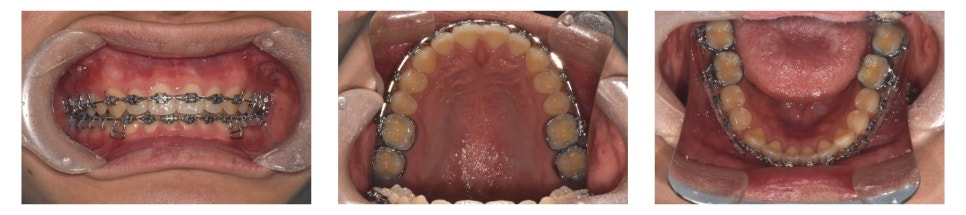

브라켓(bracket)과 밴드(band)를 부착하여 치아 배열을 진행하였습니다.

깊게 물리는 상태라 하악 치아에 장치를 바로 부착하면 상악 치아에 걸릴 수 있었습니다.

따라서 상악 먼저 장치를 부착하여 배열을 시작했습니다.

약 4개월 후 상악 배열이 어느 정도 진행되면서, 하악에도 장치를 부착할 수 있는 공간이 확보되었습니다.

이후 하악에도 장치를 부착하여 배열을 진행했습니다.